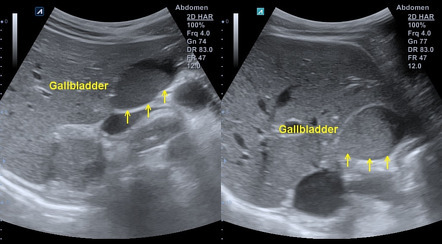

ultrasound appearance of sludge (2)

A

low-level “sandy” echoes

moves slowly with patient repositioning

ultrasound appearance of sludge balls

avascular mass with low-level echoes